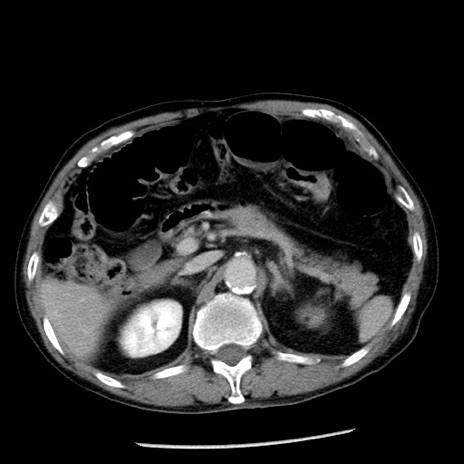

症例26(横断像)

【症例】80歳代男性

【主訴】嘔吐

【現病歴】昨晩2回嘔吐あり、今朝になっても嘔吐あり。来院。

【既往歴】胃潰瘍

【身体所見】意識清明、BT 37.6℃、BP 166/95mmHg、HR 100bpm、SpO2 97%、腹部:平坦・軟、腸蠕動音聴取良好、圧痛なし。

【データ】WBC 21900、CRP 1.46